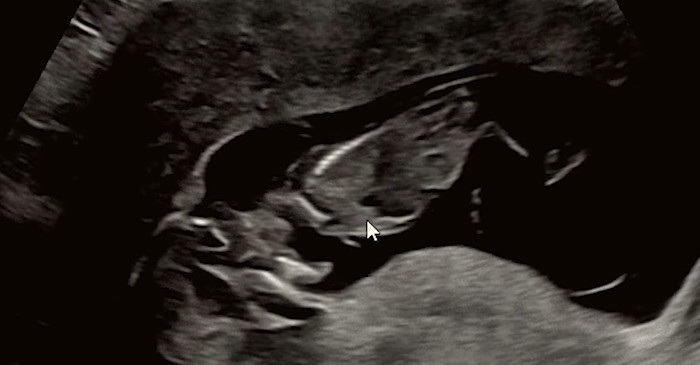

カン・ウンビは動画を通じて3日に胎児を見送ったと明らかにした。彼女は妊娠経過中の定期検診で全ての数値が正常だという説明を受けたが、その後羊水が減少したという見解を受けたと説明した。検査過程で羊水漏出の可能性が指摘され、上級病院に搬送され、入院後2日目に羊水の数値が0という診断を受けたと伝えた。

カン・ウンビはその病院で胎児が横向きに寝ており、胎盤に密着している状態で、肺の発達がこれ以上難しい状況だという説明を受けたと伝えた。医療陣は胎児が非常に限られた空間で耐えている状態だと判断した。